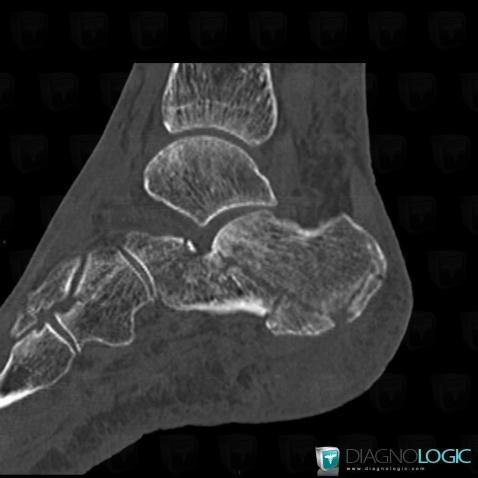

Fracture, Calcaneus, X rays

Here is the specific information in the key image above:

- Diagnosis Fracture, Location(s) Calcaneus, with gamuts